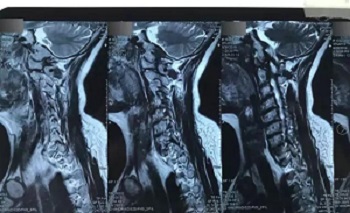

八、拍片子时,如果一张片子上有两张图像的时候,合起来拍一张,分开再各拍一张(如以下三张)

十一、将分区的磁共振图像,按顺序进行拍摄,即可获取如下比较有价值的清晰图片

(区域1)

(区域2)

(区域3)